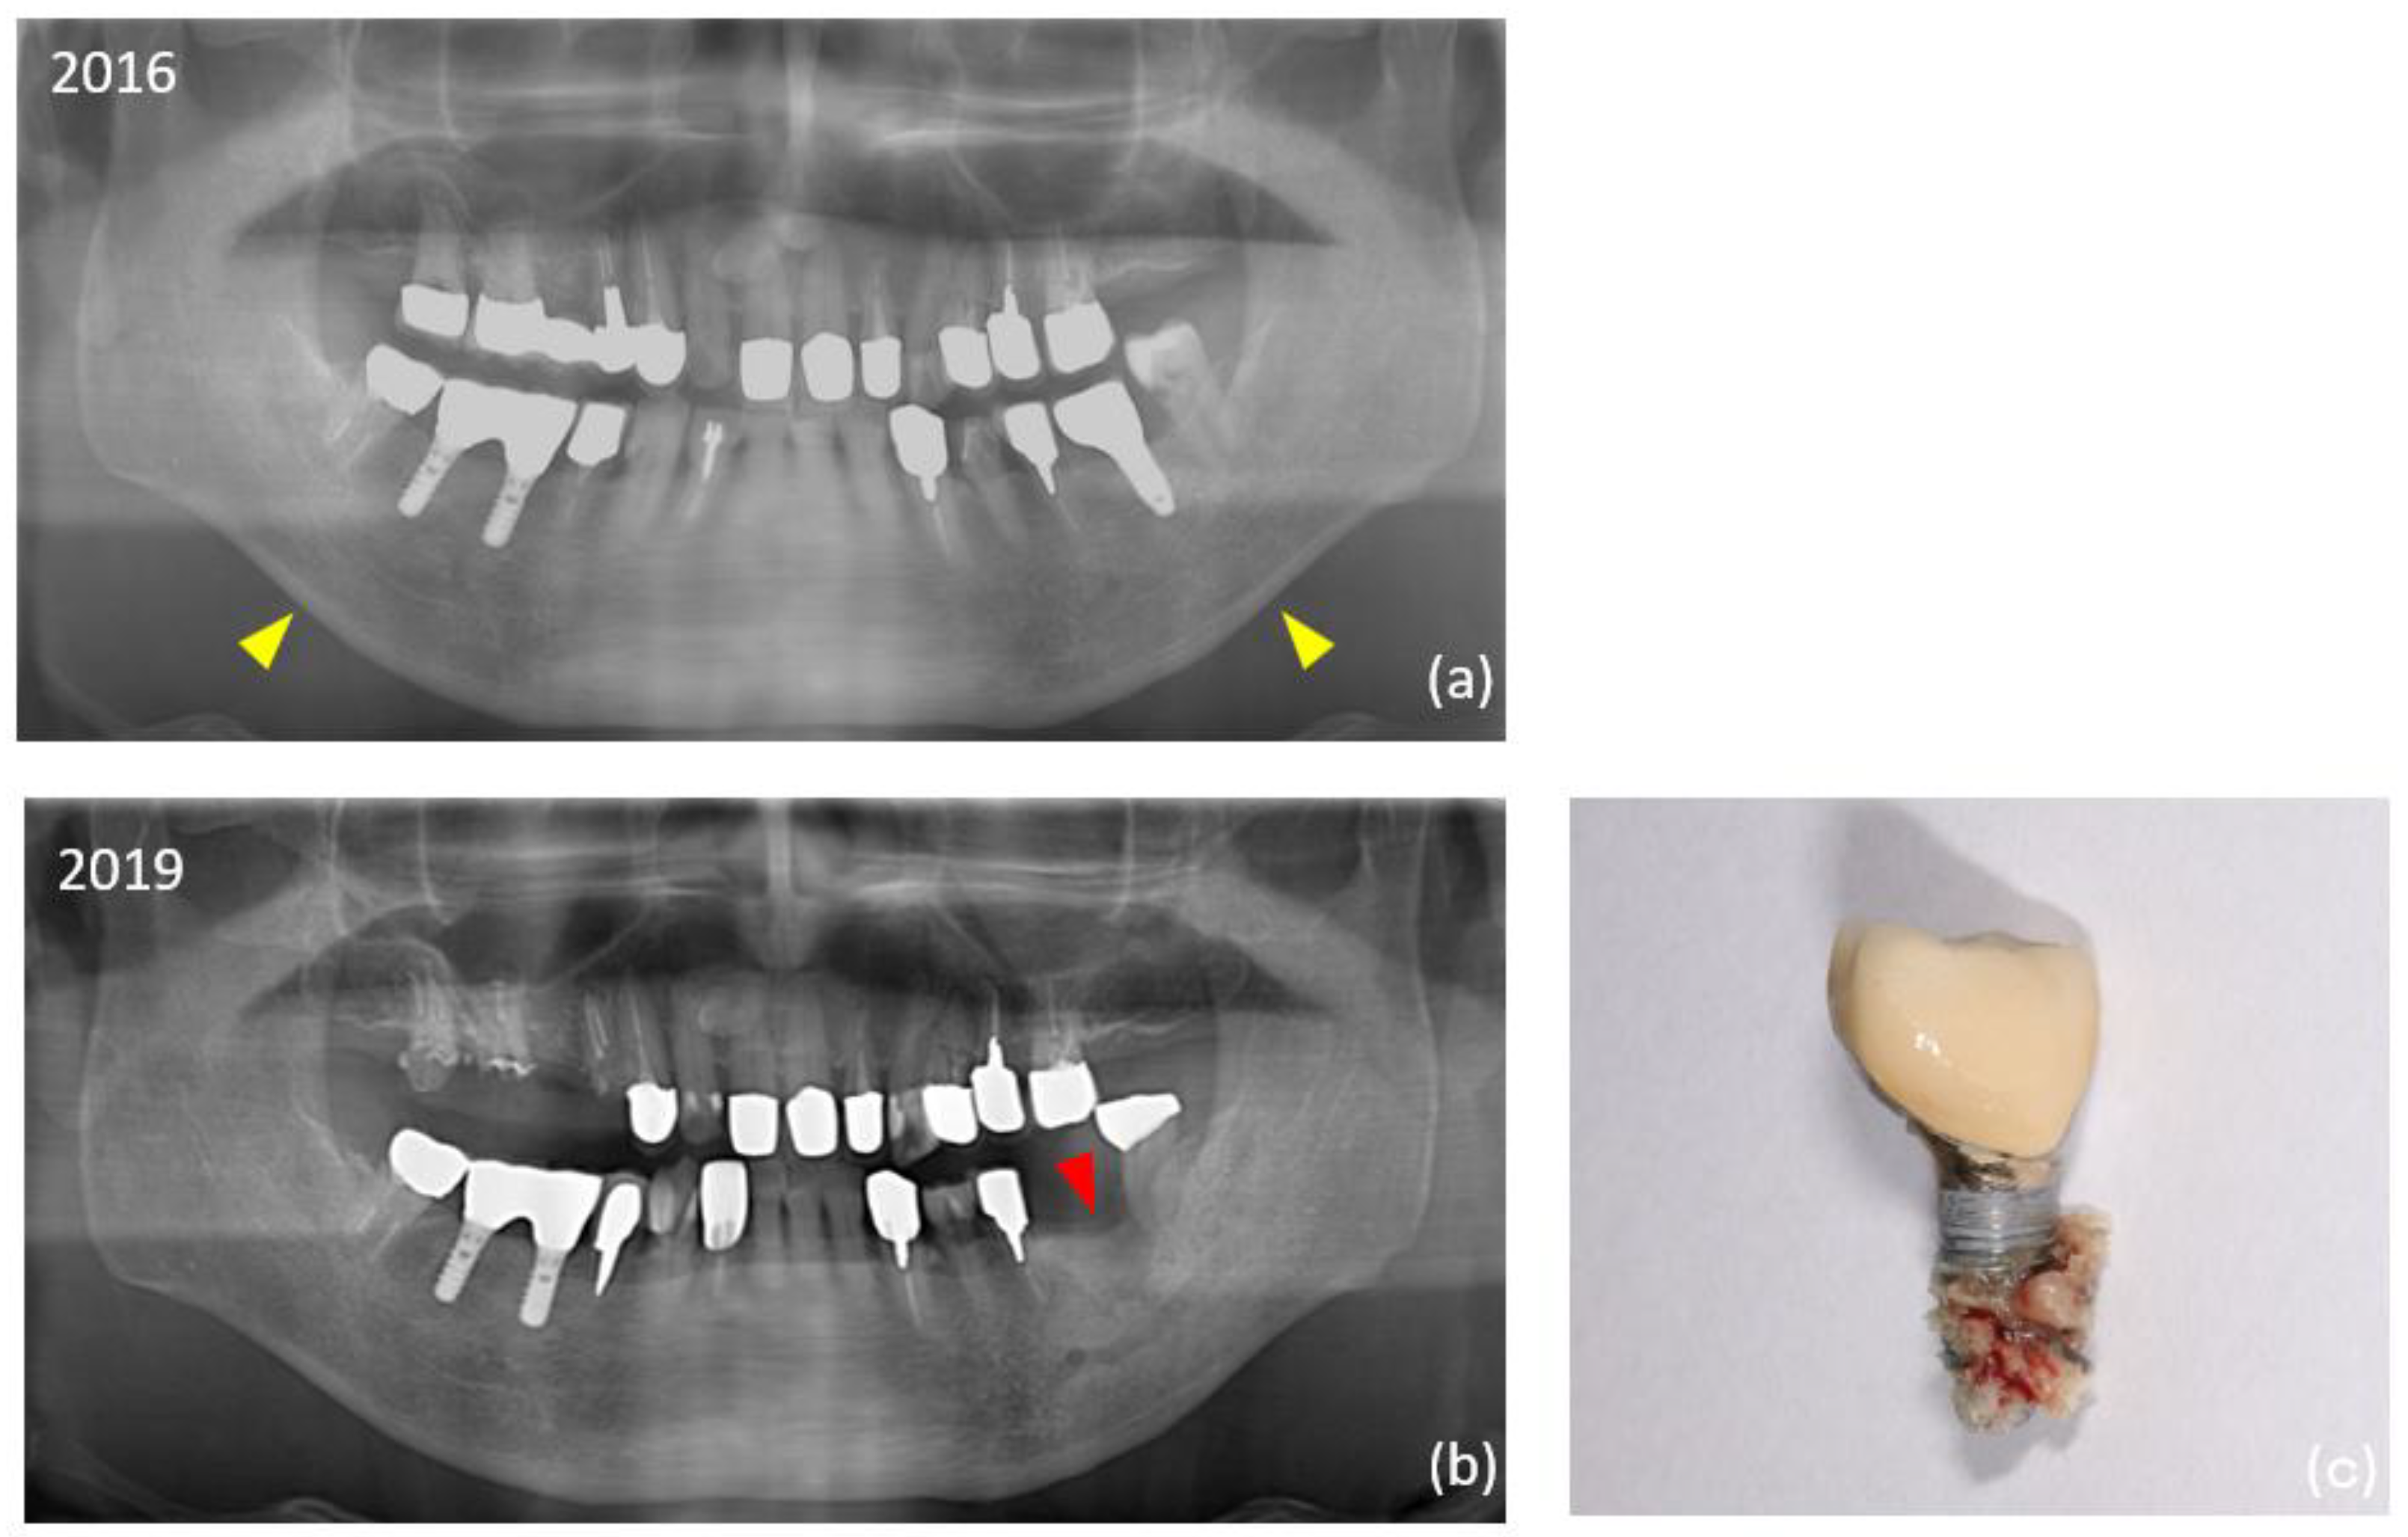

Information at the implant level for each group is shown in Table 2. There were no significant differences between the two groups in superstructure type, or in the dimensions of the implants placed. In additional surgeries, the split crest technique was significantly more common in the control group. The overall mean observation period for implants was 13.2 ± 6.4 years, which was significantly longer in the ARA group (14.7 years) than in the control group (11.8 years). The overall prevalence of peri-implantitis was 18.2% (35 of 192 implants) at the implant level and 13.1% (8 of 61 patients) at the patient level, significantly higher in the ARA group (28.1% within the group: implant level). Thirteen (6.8%) of the total 192 failed implants occurred during the study period. Peri-implant MRONJ developed in two patients in the ARA group (4 implants in total) (Figure 2). Details of the ARA group are shown in Table 3.

Figure 2. Digital panoramic radiography imaging findings in an 88-year-old man (Case 20). (a) The #36 implant was placed in 2010. The mandibular cortical index (MCI) classification was class 2 (yellow arrowhead). Class 1; a smooth cortical bone inner surface, class 2; an irregular inner surface of cortical bone with linear resorption, and class 3; severe linear resorption and cortical bone rupture over the entire cortical bone. (b) The patient started using an antiresorptive agent in 2017. The implant was removed in 2019 (red arrowhead). (c) The patient was diagnosed with stage 2 peri-implant medication-related osteonecrosis of the jaw (MRONJ).